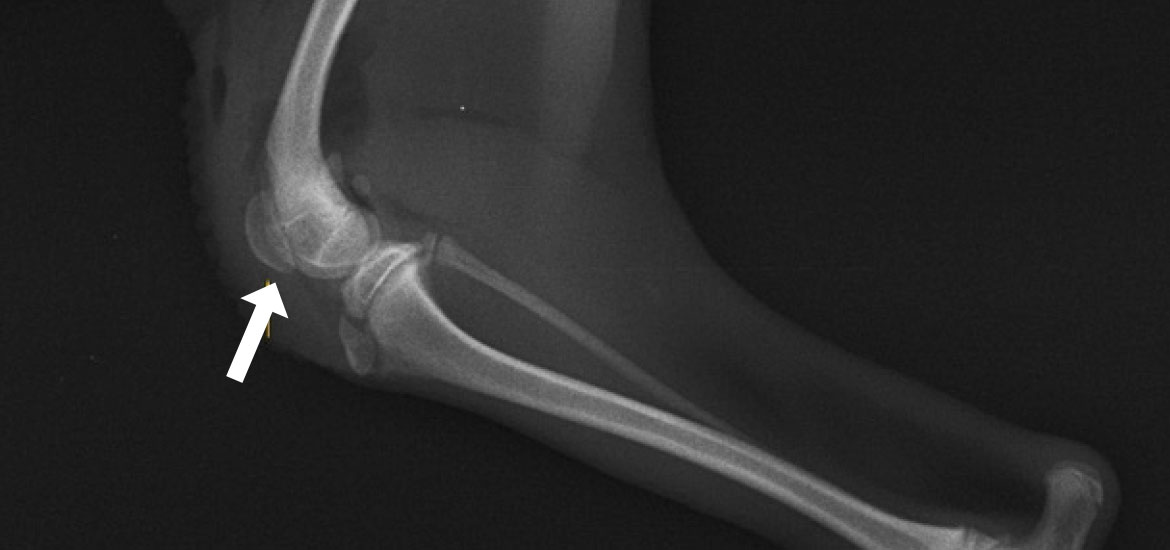

内方脱臼(右後肢)

-

Before

膝蓋骨が内側(内方)に変位しています -

After

膝蓋骨が正常な位置(正中)に整復されています